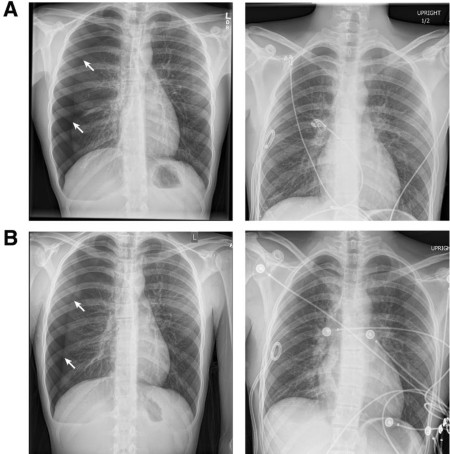

Report of the Month: Recurrent spontaneous pneumothoraces and vaping in an 18-year-old boy

Primary spontaneous pneumothorax (PSP) is a common disorder occurring in young adults without underlying lung disease. Although tobacco smoking is a well-documented risk factor, an association between electronic cigarette use (that is, vaping) and PSP has not been noted. This report covers a case of an 18-year-old boy presented with recurrent right-sided spontaneous pneumothoraces twice in two weeks. He reported a history of vaping just prior to both episodes. (Bonilla et al., 2019)